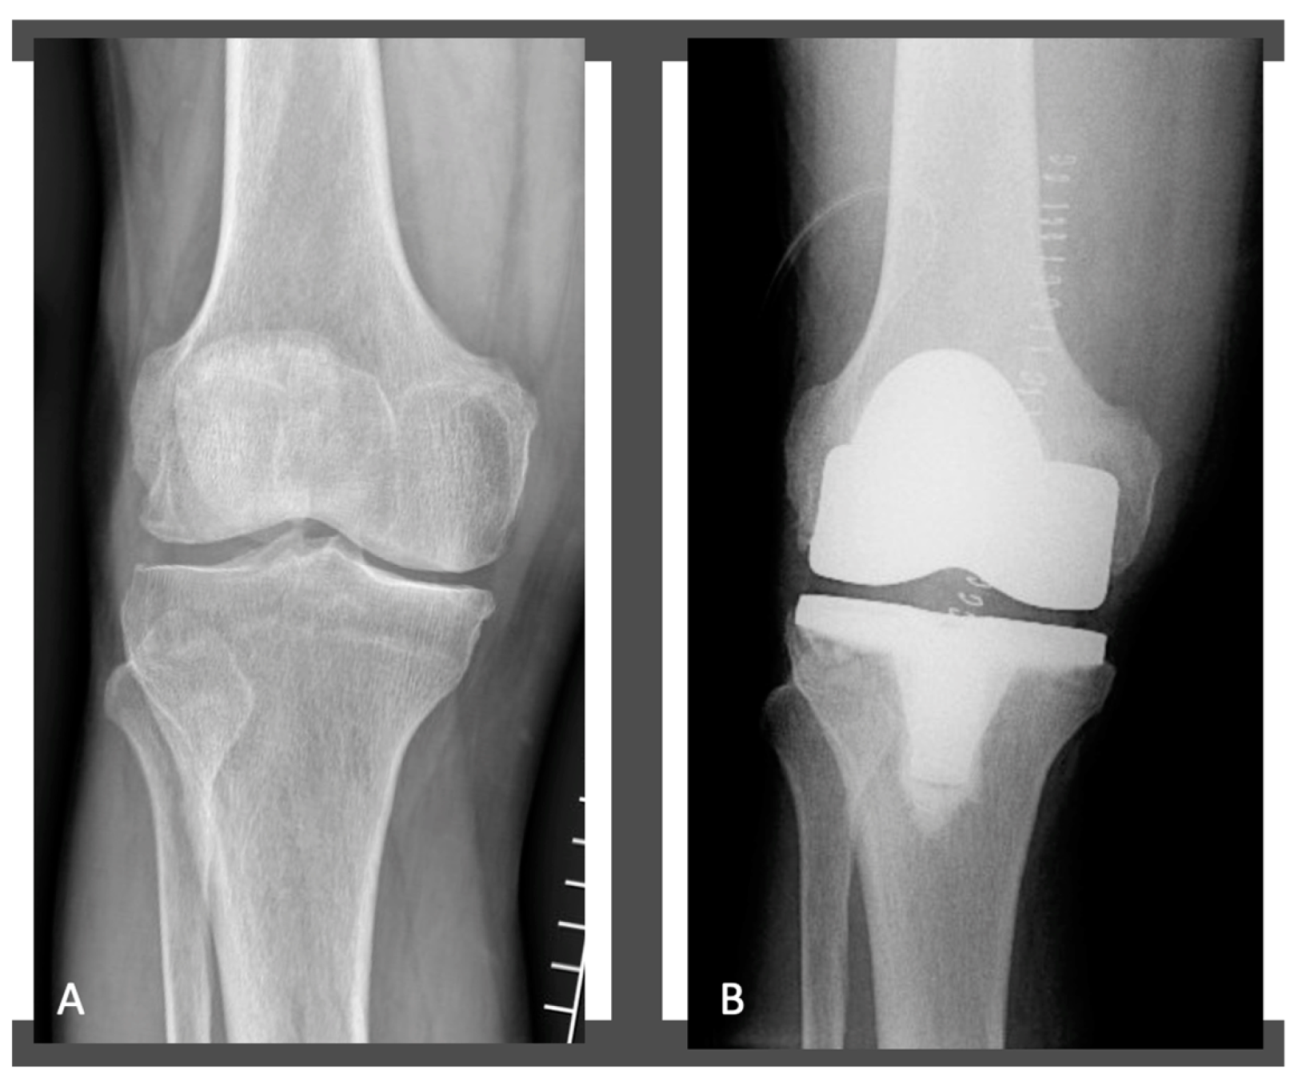

2.3. Surgical Technique